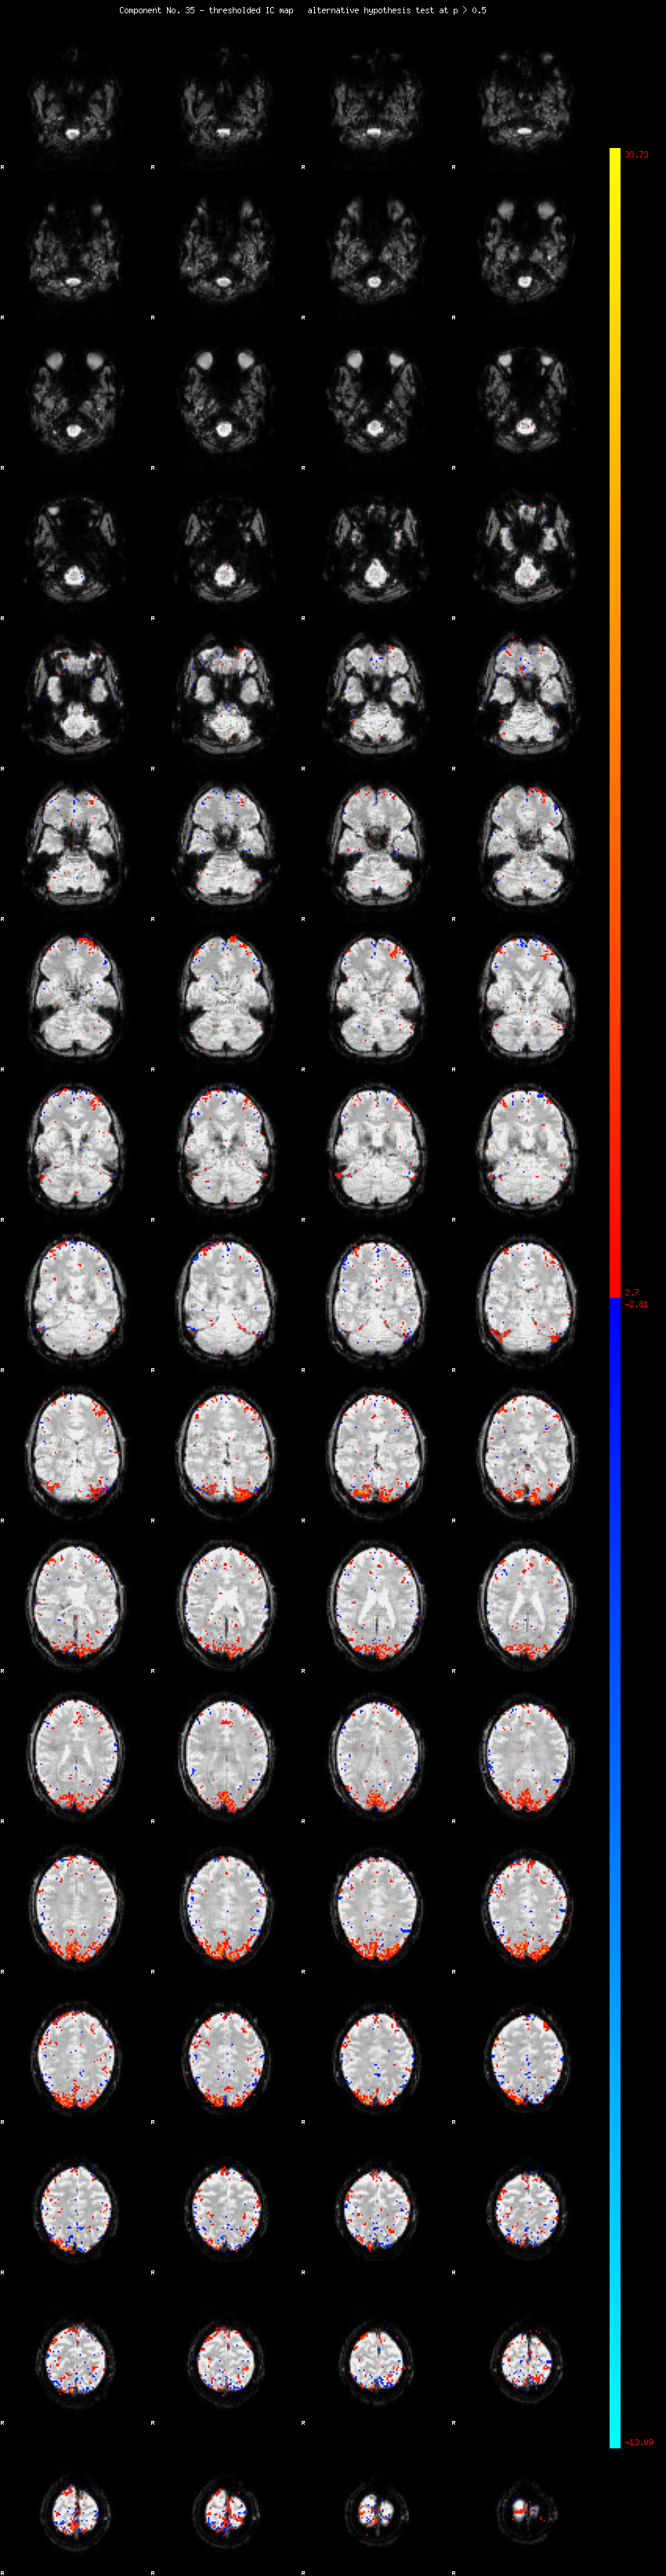

MELODIC Component 35

1.17 % of explained variance;     0.78 % of total variance